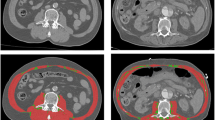

For segmentation, the CT image files were extracted and uploaded into Slice-O-Matic, where sagittal views were reproduced from axial slices. The thoracic vertebrae were manually identified by locating the most cranial vertebra with protruding ribs attached anteriorly to the sternum, identified as the first thoracic vertebra, and counting down. The lumbar vertebrae were manually identified by locating the sacrum and counting up to the last thoracic vertebra with protruding ribs, with the highest lumbar-like vertebra considered the first lumbar vertebra. Following the identification of vertebral levels on sagittal view, automated measurements of total SMA and IMAT were made on axial view immediately above the aortic arch (AbvAoAr; Fig. 2a) and the mid-vertebral body of the eighth thoracic vertebra (T8; Fig. 2c), T12 (Fig. 2d), and L3 (Fig. 2e). In addition, manual SMA and IMAT measurements were made of the pectoralis major and minor unilaterally at AbvAoAr using the ranges of -29 to + 150 HU and − 190 to -30 HU, respectively (Fig. 2b).

Tagged computed tomography axial images above the aortic arch (AbvAoAr; (A), unilateral total; (B), unilateral pectoralis) and at the eighth thoracic (T8; C), twelfth thoracic (T12; D), and third lumbar (L3; E) vertebrae. Measurements AbvAoAr were made unilaterally on the right unless a right-sided device was present (F). The tagged tissues were skeletal muscle (red), intermuscular adipose tissue (green), subcutaneous adipose tissue (teal), and visceral adipose tissue (yellow)

Measurements AbvAoAr (both automatic and manual) were unilateral right-sided, given the prevalence of cardiovascular implantable electronic devices (CIEDs) in patients with HF on the left chest, but the left side was used when issues were encountered on the right side (Fig. 2f). Frequent reasons for left-sided measurements included right chest devices and hardware, poor chest and arm muscle differentiation, muscle of interest being cut out of the right image border, and high right intravenous contract load. Measurements at all other vertebral levels were bilateral. A subgroup analysis was performed comparing the correlation of total unilateral AbvAoAr to L3 measurements in patients with and without CIEDs to assess the effect of device presence.